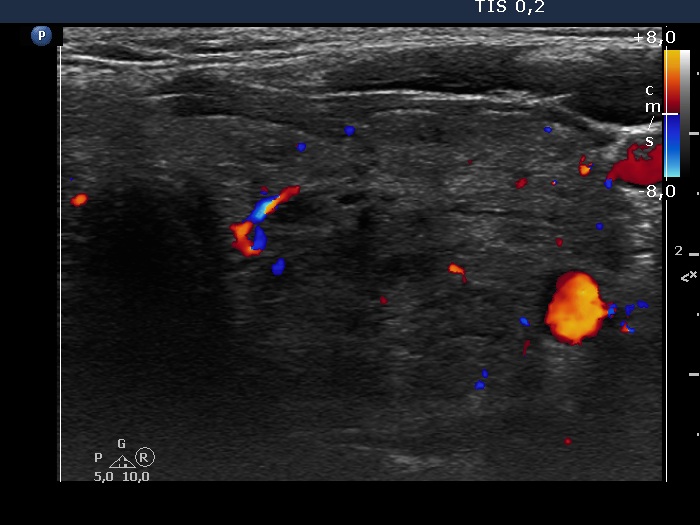

Study on 100 consecutive patients with thyroid nodule - case 053 (ultrasonographic picture 7)

Left lobe, transverse view, color Doppler mode. The moderately hypoechogenic lesion has signs of perinodular blood flow.